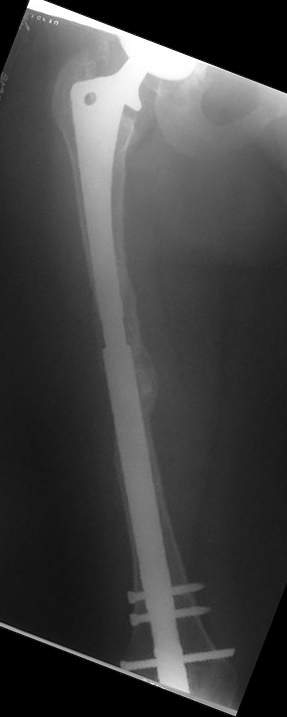

Although, there is just one view, it seems that cement is still holding well on lateral side, cup also seems to be stable, but inside is asymmetric – poly is damaged ... options:

1. "Easy": long lateral plate and anterior strut allograft w/wo bone grafting

2. "Harder" Removal of prosthesis (has to be done if it is loose in remnant of intact proof proximal femur), and new long stem, porous coated prosthesis with new cup (pt is 59years old, probable in good health – survived 6 weeks of traction… this would be my 1st option)

Female, rheumatoid, THA in 2003, car accident in 2006, failed plating. Nailing in Oct 2007. The nail is solid with hollow proximal part where the stem is docked. Last images are in 1 year after

nailing.